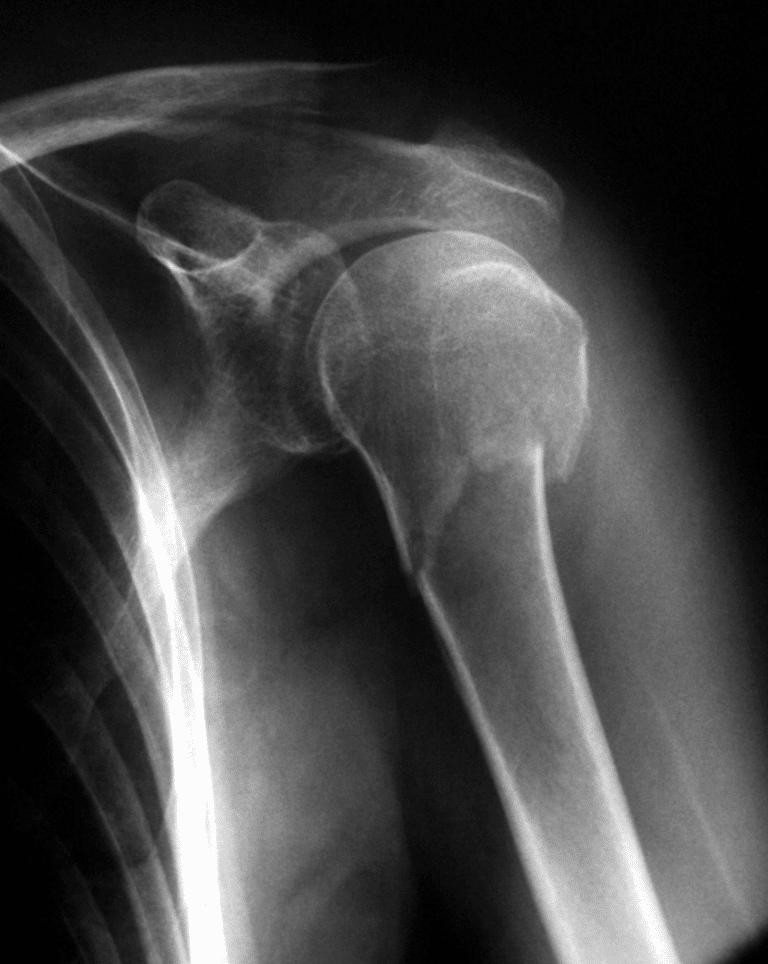

Capsulitis Hombro Después De Operación, La congelación del hombro porque sí, 21.13 MB, 15:23, 82,904, EFEsalud, 2019-01-10T16:24:29.000000Z, 3, HOMBRO CONGELADO O CAPSULITIS ADHESIVA - ALAI, www.alaismc.com, 1715 x 1704, jpeg, WebHombro congelado o capsulitis Uno de los problemas más frecuentes tras una operación de hombro es la rigidez de la articulación del hombro . En algunas intervenciones quirúrgicas es necesario un periodo de inmovilización para permitir una. WebLa capsulitis adhesiva retráctil, o más comúnmente conocida como hombro congelado, es un proceso que se caracteriza por la inflamación y retracción de toda esta cápsula. WebLa capsulitis adhesiva provoca una disminución progresiva del rango de movimiento del hombro, tanto activo como pasivo, que acaba afectando de manera., 20, capsulitis-hombro-despues-de-operacion, Novedades y Muebles WebHombro congelado o capsulitis Uno de los problemas más frecuentes tras una operación de hombro es la rigidez de la articulación del hombro . En algunas intervenciones quirúrgicas es necesario un periodo de inmovilización para permitir una. WebLa capsulitis adhesiva retráctil, o más comúnmente conocida como hombro congelado, es un proceso que se caracteriza por la inflamación y retracción de toda esta cápsula. WebLa capsulitis adhesiva provoca una disminución progresiva del rango de movimiento del hombro, tanto activo como pasivo, que acaba afectando de manera.

WebLa capsulitis adhesiva retráctil, o bien más generalmente conocida como hombro congelado, es un proceso judicial que se caracteriza por la inflamación y retracción. WebEl hombro congelado también conocido como capsulitis adhesiva es una inflamación y retracción de la capsula articular que envuelve el hombro y que causa la pérdida de. WebLa capsulitis adhesiva idiopática, u hombro congelado, debe diagnosticarse de forma temprana y correcta. Se trata de una pérdida global de movimiento glenohumeral. WebEn cuanto al inicio de síntomas en el hombro izquierdo, busque de nuevo la posibilidad de la Fisioterapia pero con esa condición ya dicha de que sea suave y progresiva.. Si. WebEl dolor en la articulación del hombro y el rango limitado de movimiento son los mayores problemas resultantes de la capsulitis adhesiva. La capsulitis adhesiva. WebLa capsulitis adhesiva, normalmente, comienza de forma muy lenta y tiene tres fases bien definidas que, combinadas, pueden durar hasta 3 años: Fase. WebCAPSULITIS ADHESIVA . Denominada también como hombro congelado o pericapsulitis, puede ser primaria o secundaria a diversas causas: traumatismo,.

WebTodo el proceso de rehabilitación después de la capsulitis debe realizarse bajo estricta supervisión médica. Si durante el desarrollo de la articulación hay dolores. WebLa capsulitis es una lesión frecuente y de curso benigno en deportistas jóvenes. Las que pueden sufrir más complicaciones son las que se producen en las. WebLa capsulitis en el hombro es un proceso gradual, donde cada vez se reduce más el rango de movimiento tanto pasivo como activo de la articulación en cuestión,.